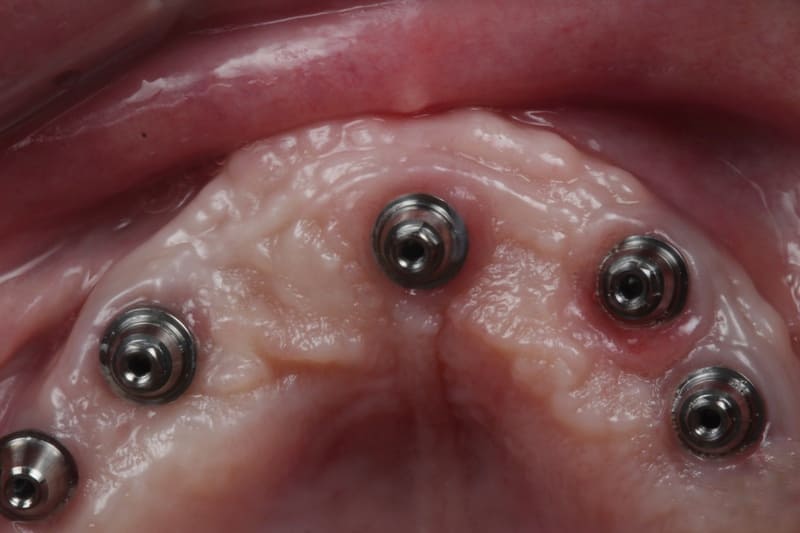

Llevamos a cabo un examen detallado de tu salud bucal, considerando la densidad ósea, la cantidad de hueso disponible y un análisis de las estructuras bucales para evaluar la posibilidad de implantes dentales.